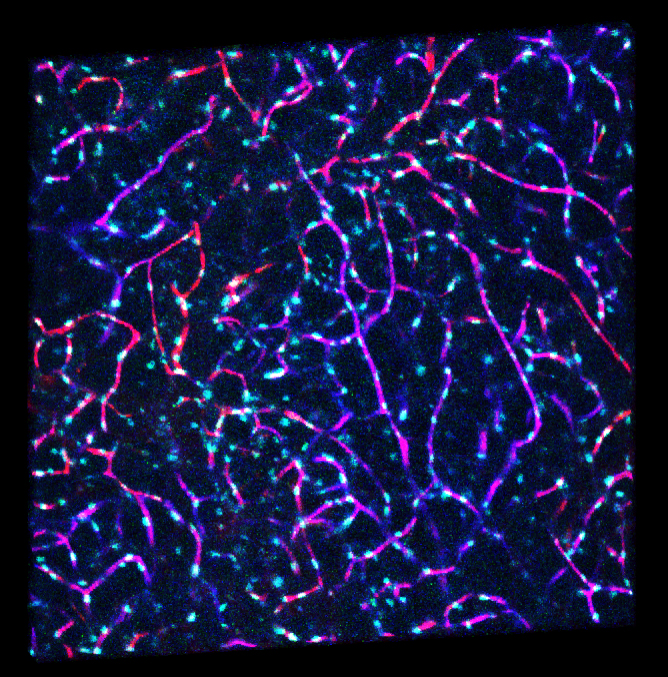

新たな「分子イメージング手法」で捉えた脂肪組織。

脂肪組織中の血管ネットワーク

生体内マルチカラーイメージングシステムの開発

我々は複雑な成人習慣病における病変にアプローチするため、独自に生体内の細胞動態をマルチカラー、高時間・空間解像度でリアルタイムで可視化するシステムを開発しました。このシステムを用いて、いかに複数の細胞種が様々な病態において機能異常を起こすかを可視化し、新たな治療法の開発に役立てます。、

今までの生体観察顕微鏡では考えられなかったレベルで、手に取るように体内での細胞の動きや働きが我々の「生体分子イメージング手法」では可視化されます。